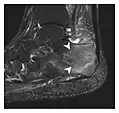

The greater tuberosity of the humerus is also an illustrative location of occult fractures. The osseous injury may follow seizures, glenohumeral dislocation, forced abduction, or direct impaction. They are commonly discovered on MRI in symptomatic patients with suspicion of rotator cuff tear. Coronal images are best suited for detection. They appear as crescentic oblique lines surrounded by a bone marrow edema pattern (Figure 5). The rotator cuff must be inspected since associated ligamentous lesions are common. In the ankle, malleoli and tarsal bones should be checked carefully for any cortical disruptions and radiolucent lines that may reveal a fracture. Awareness of the exact location of the pain will help direct the attention of the interpreter when searching for very subtle signs of fracture (Figure 6).[1]

Figure 6: Subtle anterior talar fracture in a 39-year-old man presenting with ankle pain after a fall. (a) Anteroposterior radiograph shows a subtle oblique radiolucent line through the talus (white arrows). (b) Sagittal CT reformation confirms the presence of an anterior talar fracture with cortical offset (black arrow). Avulsion fractures, which consist of a detached bone fragment resulting from a ligament or tendon pulling away from the bone, may also present with subtle radiographic signs. Tiny osseous fragments near the presumed attachment site of a ligament suggest this diagnosis. Common sites are the lateral tibial plateau (the Segond fracture), the spinal tuberosity of the tibia resulting from anterior cruciate ligament avulsion, and the ischial tuberosity.[1]